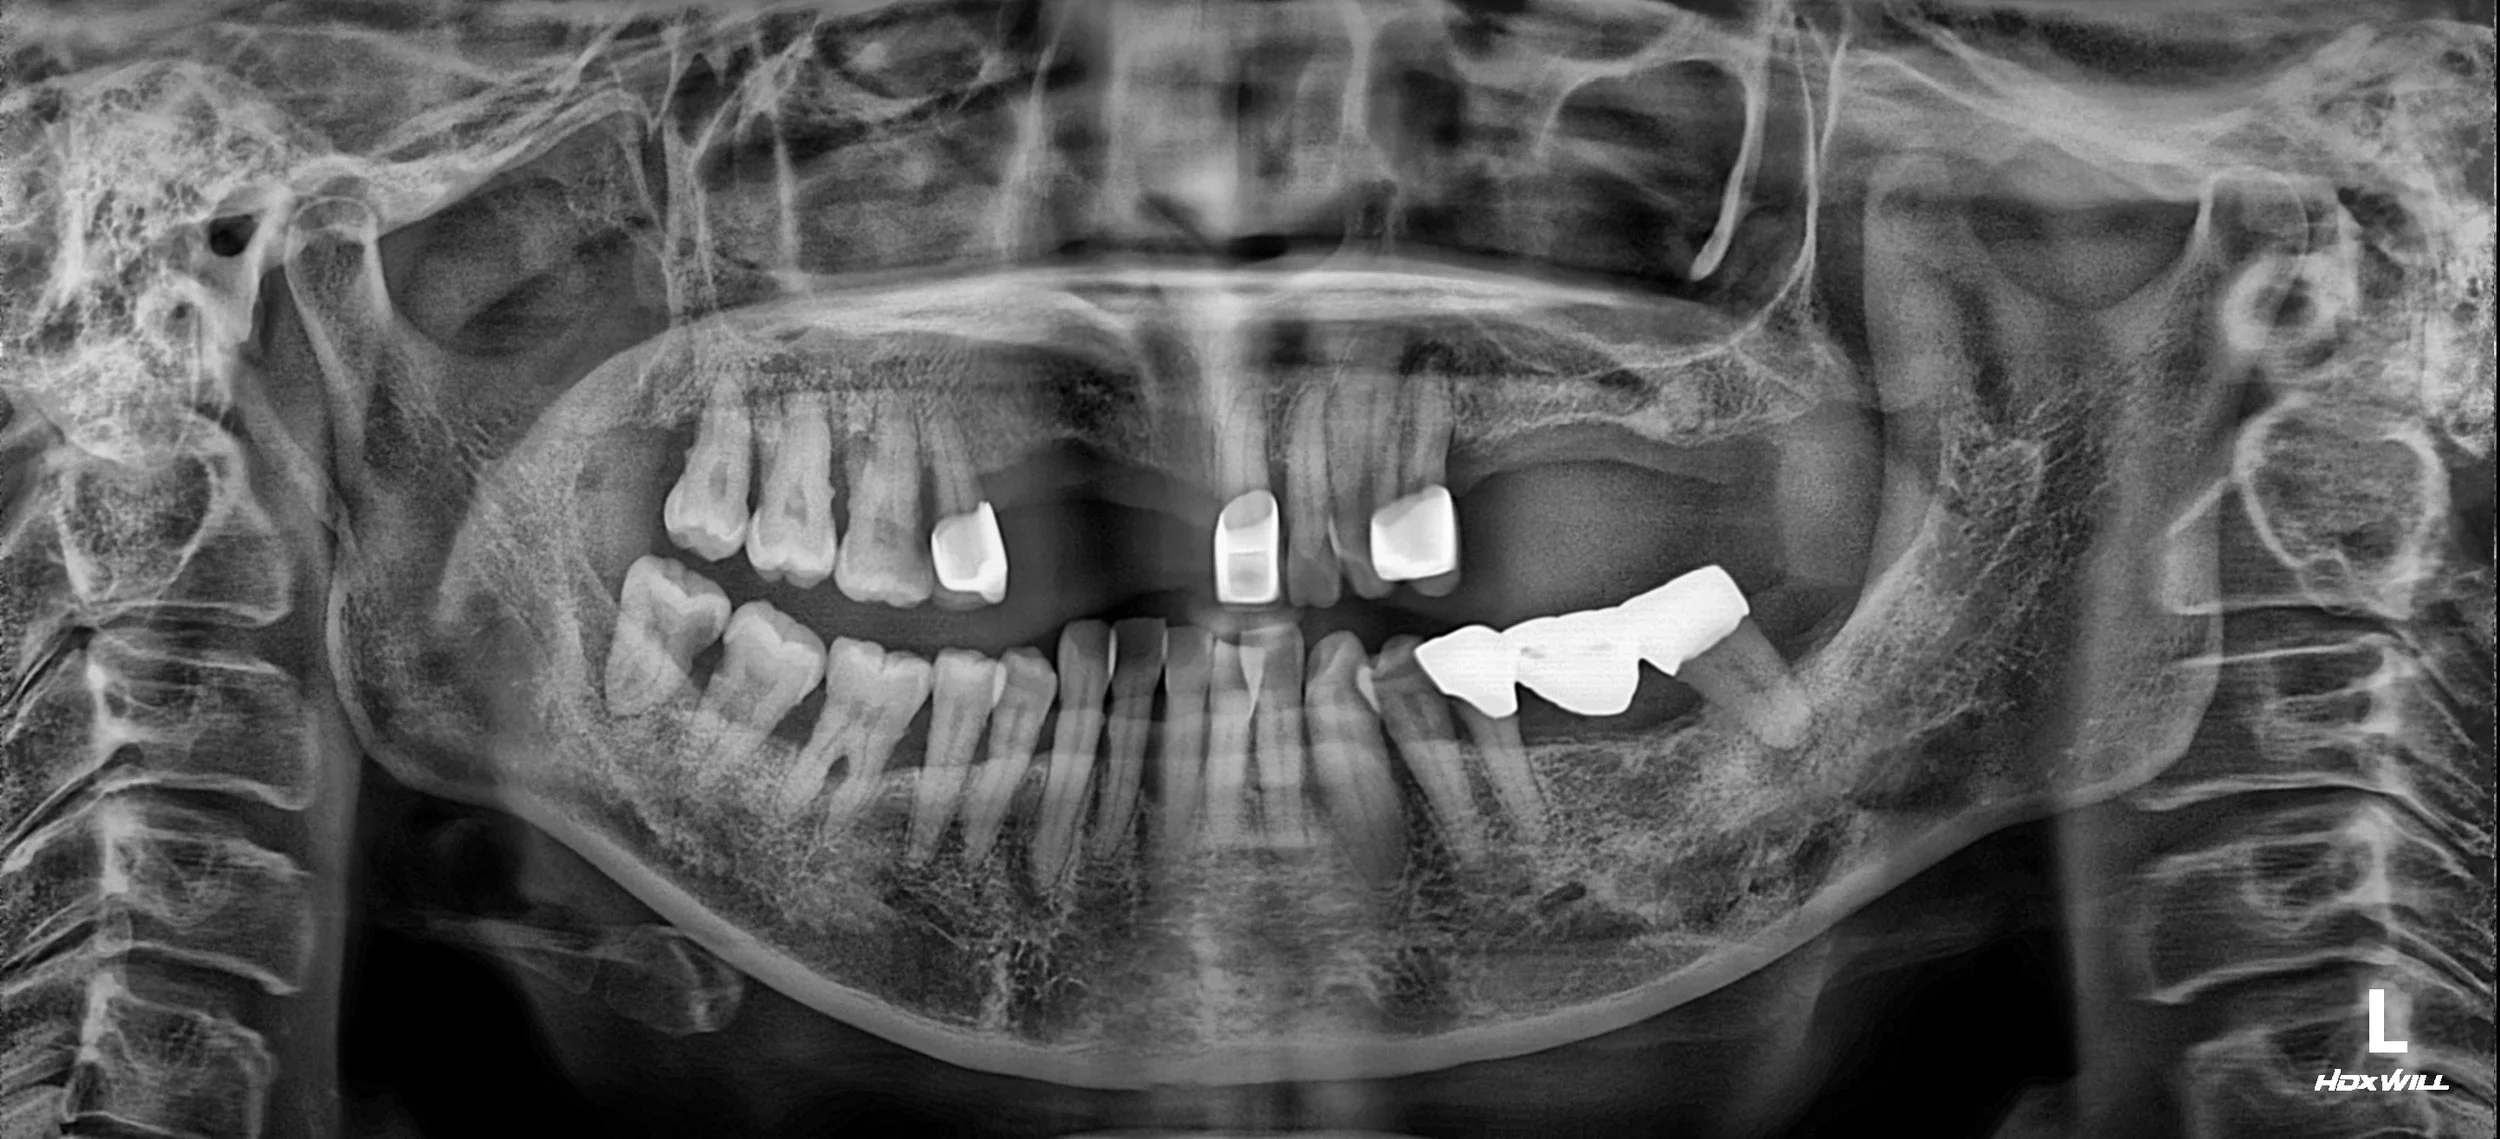

OPG - BEFORE

• Severe Alveolar Resorption: Chronic pressure from the dentures had led to extreme horizontal and vertical bone loss, particularly in the edentulous spans.

• Total Occlusal Collapse: The lack of stable posterior stops had compromised the patient's vertical dimension and chewing capacity.

• Patient Preference for Phased Care: The patient requested a sequential approach to treatment, prioritizing the most urgent edentulous areas while deferring treatment for quadrants 10 and 40.